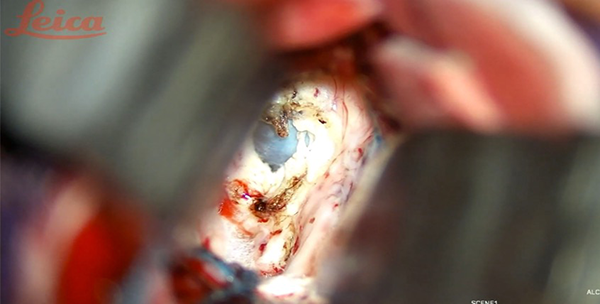

Durotomía arciforme con base al SSS, respetando componentes venosos que suelen encontrarse. Aunque estas estructuras de drenaje a lo largo del tercio anterior del SSS se consideran seguras de ligar, el riesgo de infarto venoso está descripto de forma predominante cuando son voluminosas y no hay venas suplementarias que drenen el determinado sector. En consecuencia, su manipulación y sacrificio deben mantenerse al mínimo. Se realizó drenaje del líquido cefalorraquídeo (LCR) mediante punción lumbar aproximadamente 12 cc para descomprimir el parénquima y favorecer la separación. Los retractores fijos se tratan de evitar mediante el uso de retracción dinámica, intermitente e inducida por la gravedad (rotación de la cabeza de forma que el seno sagital se posicione paralelo al suelo, o colocar al paciente en decúbito lateral). Una vez identificado el lugar apropiado para acceder a la fisura interhemisférica, comienza su disección con técnica microquirúrgica y utilizando microscopio (Leica M525 OH4), se procede a la apertura de la aracnoides con microtijera en sentido longitudinal, debiendo reconocer la circunvolución frontal superior lateralmente y el borde libre de la hoz del cerebro, inmediatamente después encontrándose la circunvolución del cíngulo. La neuronavegación permite localizar sin dificultad al cuerpo calloso, disminuyendo el tiempo quirúrgico. Puede a su vez distinguirse por el color blanco nacarado, avascular y con las arterias pericallosas sobre su cara superior, las cuales se disecan por la línea media exponiéndolo (Figura 4A). En ocasiones, éstas pueden desplazarse hacia lateral o adherirse, lo que dificulta su separación con riesgo de lesionarlas.9 La callosotomía se realiza en el tercio anterior, en sentido anteroposterior con coagulación bipolar y tijera microquirúrgica, no debiendo exceder de 20 mm, lo cual proporciona adecuada visualización del foramen de Monro, las venas cerebrales internas, coroideas y talamoestriadas.10 11 12 Esta apertura limitada generalmente no implica secuelas neuropsicológicas postoperatorias (Figura 4B-5).

Figura 5. Imagen transoperatoria: realizada la callosotomía se aprecia lesión quística* descrita.